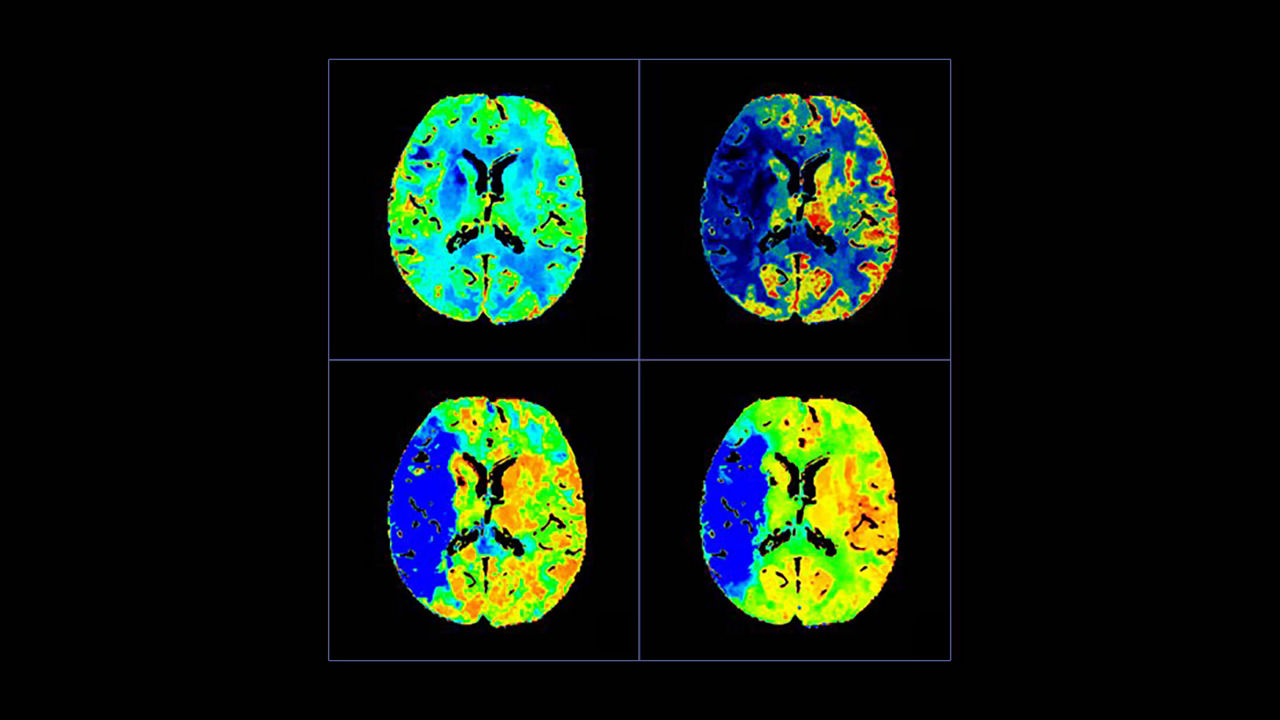

Simplify the Stroke CT workflow and the communication within the stroke team.

<p>FastStroke with StrokeSENS<sup>3</sup></p>

Learn more

<p>CT Perfusion 4D Neuro</p>

<p>Dynamic Shuttle</p>